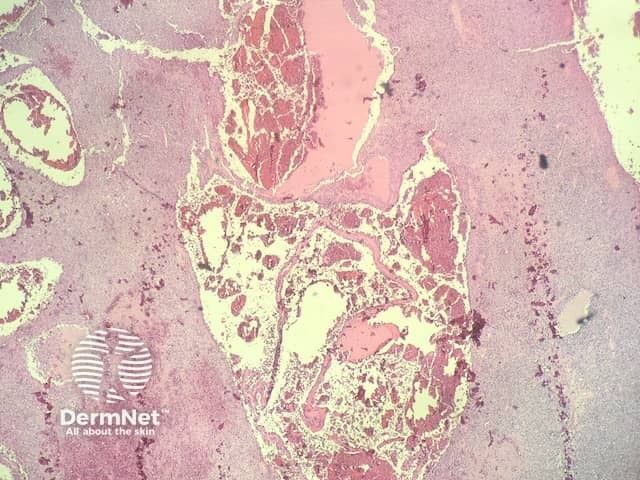

In angiomatoid fibrous histiocytoma, the histopathology shows a dense capsule surrounding the tumour and associated lymphoid aggregates (figure 1). Centrally, there are large blood filled cavities associated with surrounding haemorrhage and hemosiderin deposition (figures 2,3). In other areas, there is a solid growth of monomorphic bland spindle to ovoid eosinophilic cells (figure 4). In some areas there may be some pleomorphism and mitotic activity.

Figure 2

Figure 3